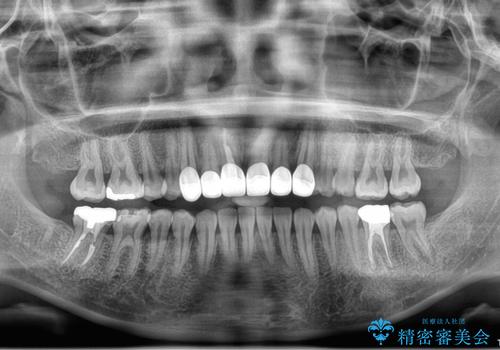

歯周組織がある程度改善されるまでに3か月ほどかかりました。

いざ型どりしていくというタイミングで、前歯の大きさが違いすぎるのが気になるとのことで歯周外科治療(アピカリ)にて歯肉のラインを整えることに。

歯肉の治りを待ったうえで(約8か月)、最終補綴することとなりました。

補綴はスペシャルです。

結果的に期間がかなりかかってしまいましたが、患者様に満足していただける結果となりました。